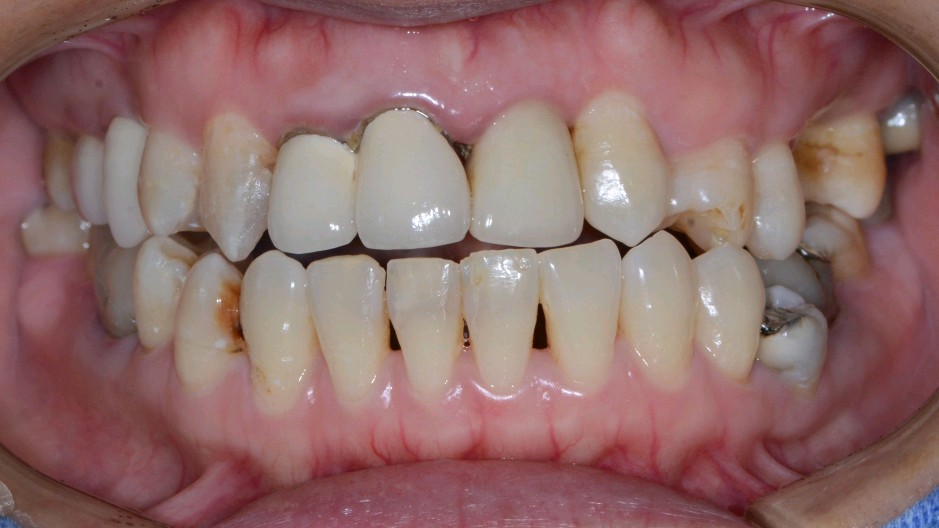

患者女,三十岁,11、12、21牙已行根管治疗,11、21烤瓷全冠修复。由于长时间烤瓷牙的佩戴,导致牙龈边缘发黑,颈缘处牙龈组织出现"黑线"。腭侧部分也出现了崩瓷的现象。对于这种情况,建议患者尽早重新修复,避免二次伤害。患者最终选择重新修复,也给出患者合理的方案,患者选全瓷冠修复,与今日佩戴完毕。边缘密合度良好,形态色泽自然美观,患者满意。

术前